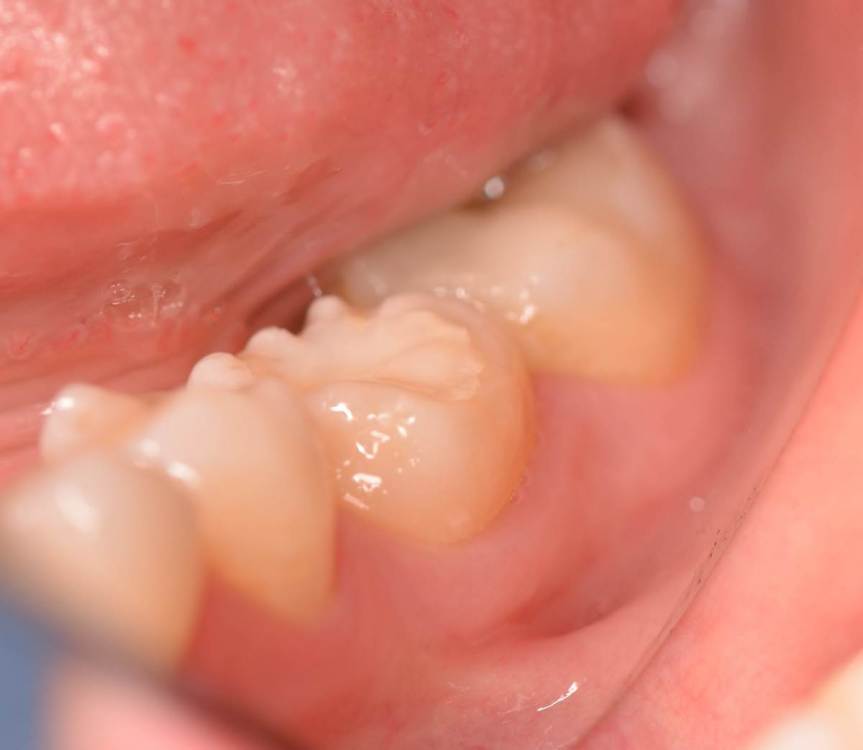

Dr.Deletle Опубликовано 22 июля, 2023 Поделиться Опубликовано 22 июля, 2023 (изменено) Этот кейс интересен тем, что у пересаживаемого 2.8 полностью сформированы корни. Пациент Н., 35лет, зуб 3.6 подлежит удалению по терапевтическим показаниям. Донором был выбран зуб 2.8. Фото №1, 2 - ситуация ДО на фото и срезе КЛКТ Фото №3 - планирование на реконструкции ОПТГ из КЛКТ Фото №4 - шаблон зуба 2.8 Фото №5, 6 - операция, удален 3.6, припасован шаблон, пересажен 2.8 (фиксирован швами и шиной к 3.7) Фото №7 - КТ сразу после пересадки Фото №8, 9 - депульпирование пересаженного 2.8 через 2 недели Фото №10 - снятие шины через 2нед после пересадки Фото № 11, 12, 13 - состояние в полости рта и на срезе КТ через год после пересадки, видно сформированное периодонтальное пространство, здоровая костная ткань, жалоб у пациента нет, полноценно жует как обычным зубом Изменено 22 июля, 2023 пользователем Dr.Deletle 4 3 Ссылка на комментарий